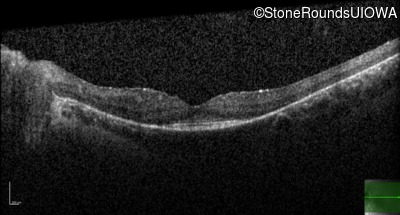

AR Retinitis Pigmentosa (IA1aiii)

Age at visit: 22 years

This 22 year old man noticed some difficulty driving at night during the past year.

Diagnosis & molecular findings

Disease Gene Allele 1 variant(s) Allele 2 variant(s) Inheritance mode

AR Retinitis Pigmentosa CLN3 Deletion Exons 9-10 Arg405Trp CGG>TGG AR